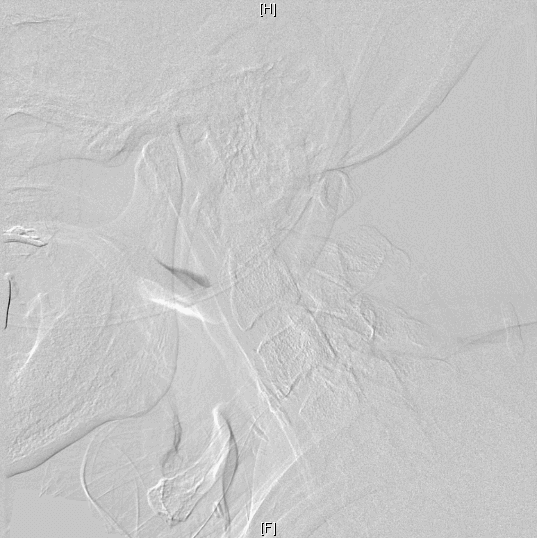

经血管评估检查确认,陈伯的彩超显示其左颈内动脉起始段狭窄达90%,血流速度>300cm/s(正常值<100cm/s),且 DSA证实左侧颈内动脉极重度狭窄(接近闭塞),仅依靠微弱的侧支循环维持脑部供血。“虽然血管尚未完全闭塞,但残余血流已无法满足正常生理需求。更危险的是,斑块表面的血栓或粥样硬化成分碎屑被血流冲至颅内,恰好堵塞左侧大脑语言中枢的供血动脉,最终引发急性脑梗死。”郑峥说。

“经过脑血管造影证实后,我们立即着手为患者设计左侧颈内动脉支架植入术方案。这是一种通过右侧股动脉入路的微创介入手术,旨在开通狭窄血管、恢复脑部供血。”

术前(上)、术后(下)影像对比